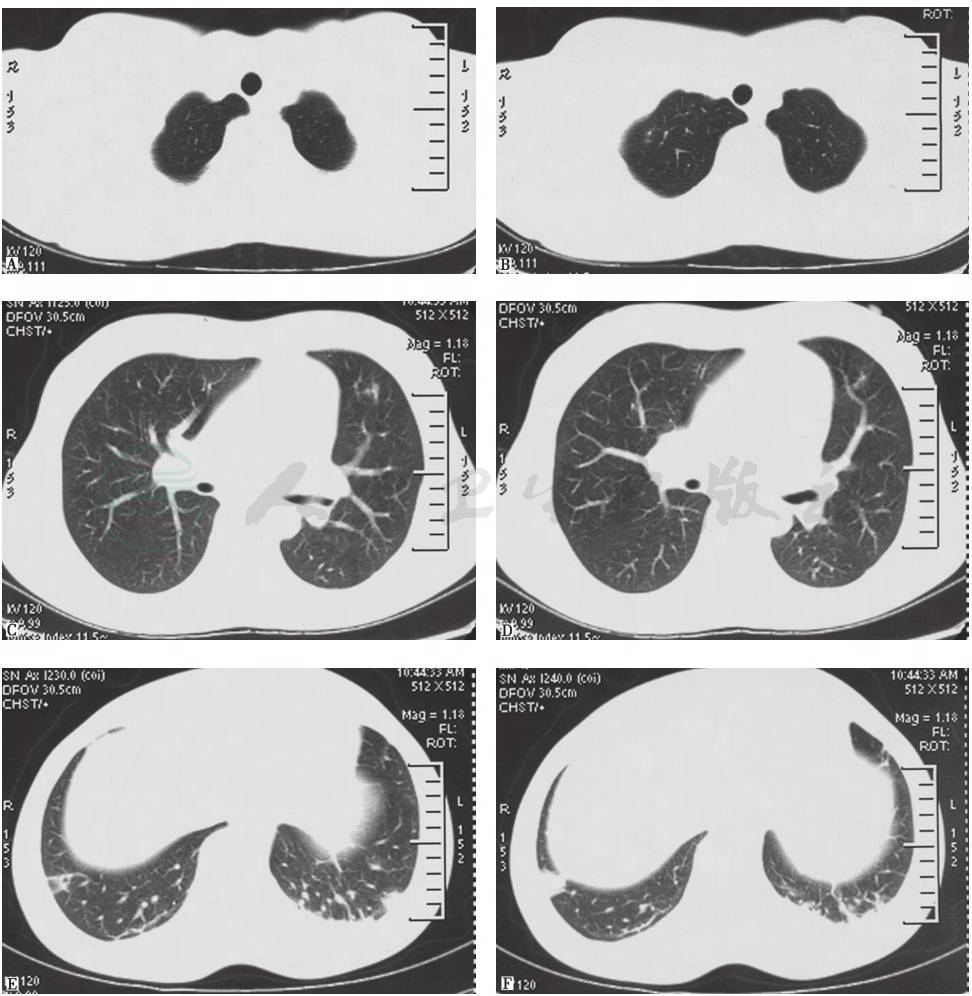

胸部CT(2015年1月6日):双肺多发高密度影,右下肺明显,双侧少量胸腔积液,肺动脉增宽,纵隔未见肿大淋巴结影(图3)。

图3 胸部CT表现(2015-01-06)

胸部CT(2015年3月1日):仅见右肺小结节影、索条影,右下肺近肋膈角处高密度楔形影,未见胸腔积液(图5)。

图5 胸部CT表现(2015-03-01)

肺动脉增强CT(2015年3月20日):肺动脉宽3.5cm,肺动脉主干左侧内壁略毛糙,可见点状充盈缺损区(图8)。与2015年1月6日胸部CT相比,左肺下叶有新出现的多发病灶,原多发感染病灶大部分有所吸收,原右侧胸腔积液吸收(图9)。

图9 胸部CT表现(2015-03-20)